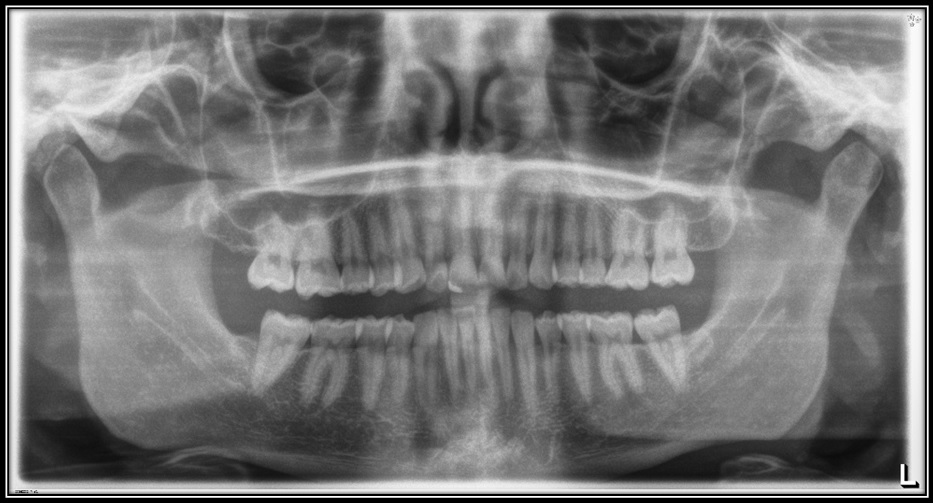

Panoramic X-rays show the entire mouth area — all the teeth in both the upper and lower jaws — on a single X-ray. This type of X-ray is useful for detecting the position of fully emerged as well as emerging teeth, can identify impacted teeth, and aid in the diagnosis of tumors